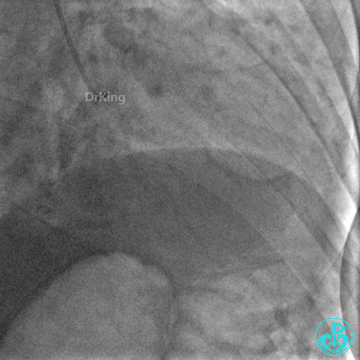

右冠脉支架通畅无狭窄,右冠脉给前降支远端提供逆向侧支循环。

EBU指引导管左冠脉造影显示粗大前降支中段闭塞,闭塞段近端有对角支发出,前降支同侧逆向显影,闭塞段不长。